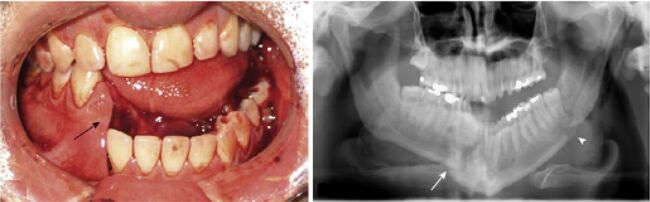

45.對於附圖的骨折說明,何者最適當?①compound fracture ②complex fracture ③simple fracture (A)僅① (B)①② (C)①③ (D)②③

78.附圖兩張X光片所呈現的影像,其臨床診斷最可能是下列何者? (A)纖維性發育不良(fibrous dysplasia) (B)淋巴結(lymph node) (C)造釉細胞瘤(ameloblastoma) (D)涎石病(sialolithiasis)